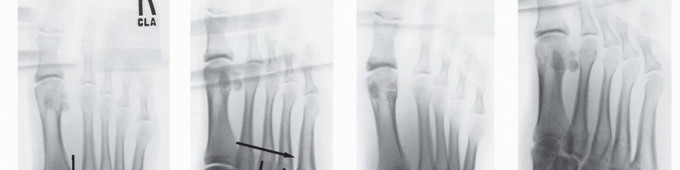

Computed tomography (CT) scanning may also be beneficial in the instance of a subtle Lisfranc injury, particularly in a polytrauma patient or a patient with multiple extremity injuries that preclude weight-bearing radiographs, and in delineating proximal fracture line extension into the navicular, cuboid, or cuneiforms (

FIG 4

).

• CT scan showing displacement through second tarsometatarsal and intercuneiform articulations (

A

) and intra-articular fractures of navicular and cuboid (

B

,

black arrows

) in a different patient.